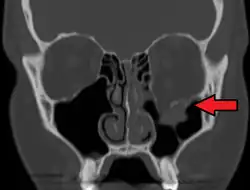

Radiography, imaging of tissues using X-rays, is used to rule out facial fractures.[2] Angiography (X-rays taken of the inside of blood vessels) can be used to locate the source of bleeding.[11] However the complex bones and tissues of the face can make it difficult to interpret plain radiographs; CT scanning is better for detecting fractures and examining soft tissues, and is often needed to determine whether surgery is necessary, but it is more expensive and difficult to obtain.[4] CT scanning is usually considered to be more definitive and better at detecting facial injuries than X-ray.[3] CT scanning is especially likely to be used in people with multiple injuries who need CT scans to assess for other injuries anyway.[12]

Commonly injured facial bones include the nasal bone (the nose), the maxilla (the bone that forms the upper jaw), and the mandible (the lower jaw). The mandible may be fractured at its symphysis, body, angle, ramus, and condyle.[4] The zygoma (cheekbone) and the frontal bone (forehead) are other sites for fractures.[13] Fractures may also occur in the bones of the palate and those that come together to form the orbit of the eye.

At the beginning of the 20th century, René Le Fort mapped typical locations for facial fractures; these are now known as Le Fort I, II, and III fractures (right).[7] Le Fort I fractures, also called Guérin or horizontal maxillary fractures,[14] involve the maxilla, separating it from the palate.[15] Le Fort II fractures, also called pyramidal fractures of the maxilla,[16] cross the nasal bones and the orbital rim.[15] Le Fort III fractures, also called craniofacial disjunction and transverse facial fractures,[17] cross the front of the maxilla and involve the lacrimal bone, the lamina papyracea, and the orbital floor, and often involve the ethmoid bone,[15] are the most serious.[18] Le Fort fractures, which account for 10–20% of facial fractures, are often associated with other serious injuries.[15] Le Fort made his classifications based on work with cadaver skulls, and the classification system has been criticized as imprecise and simplistic since most midface fractures involve a combination of Le Fort fractures.[15] Although most facial fractures do not follow the patterns described by Le Fort precisely, the system is still used to categorize injuries.[5]